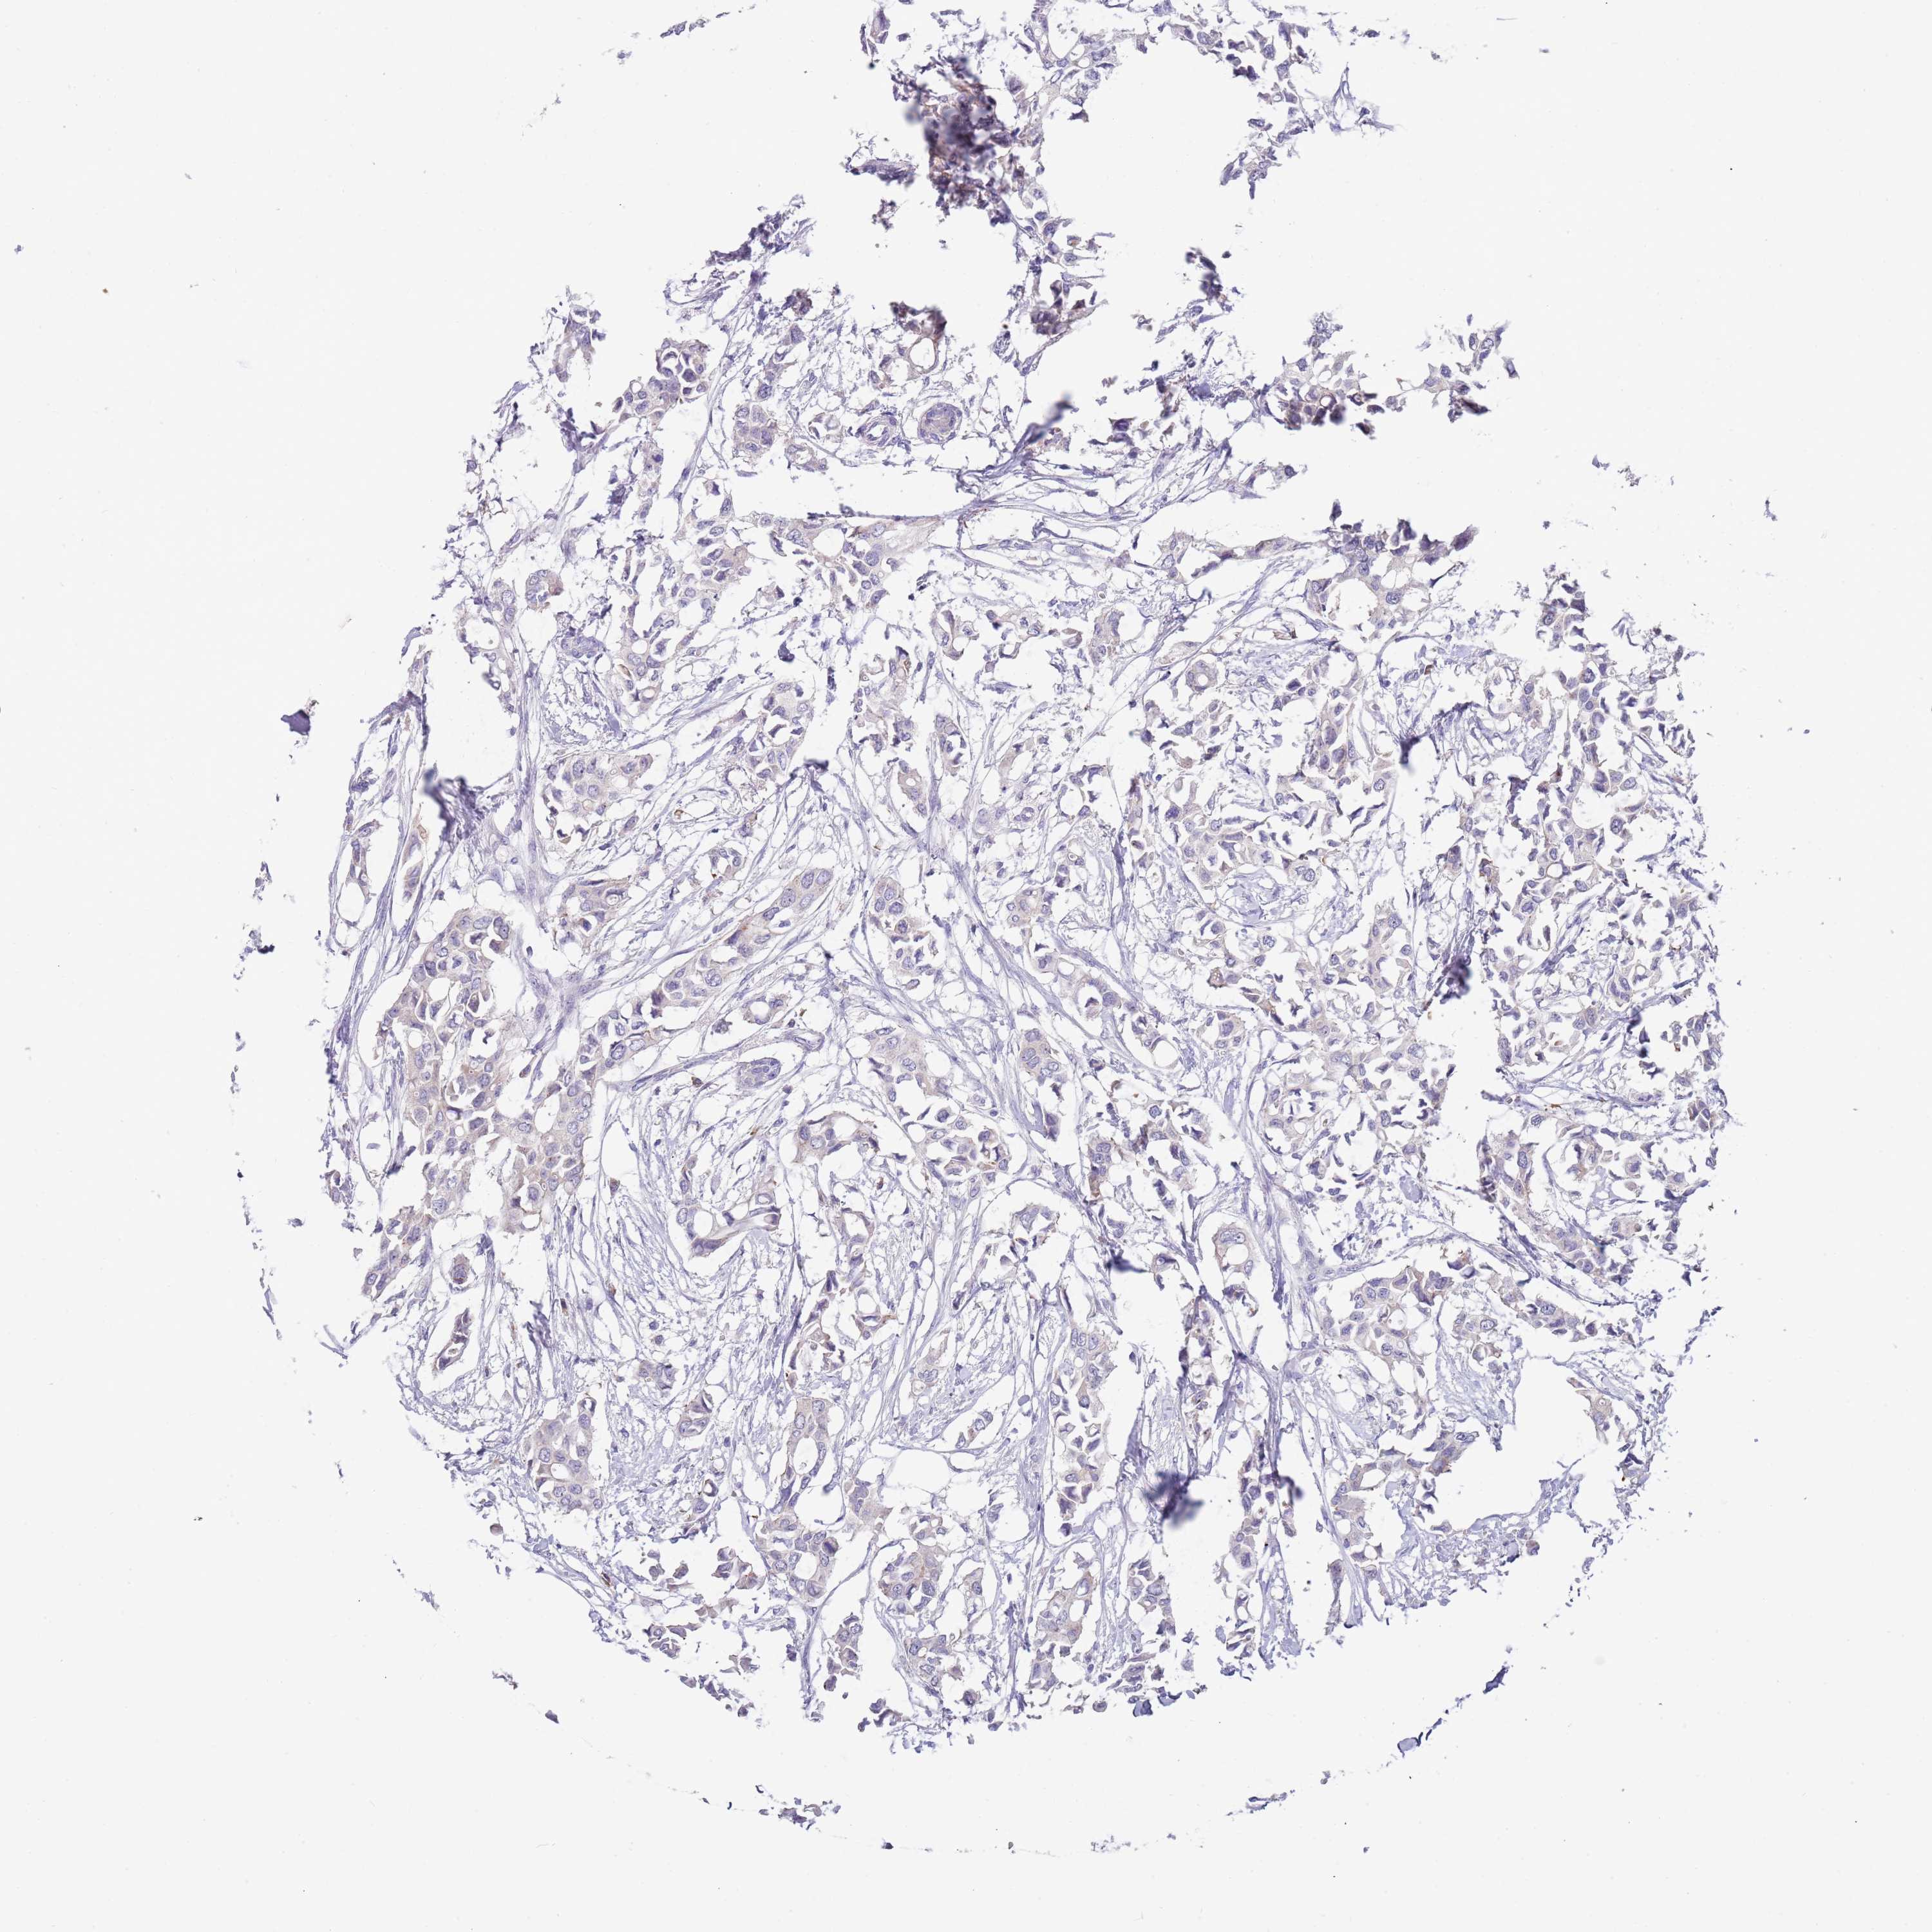

CANCER BREAST CANCER Show tissue menu

BRCA TCGA BRCA VALIDATION PROTEIN EXPRESSION